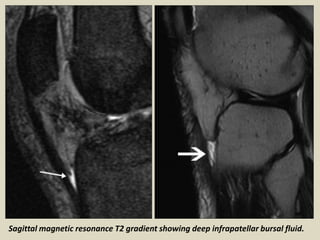

Deep Infrapatellar Bursitis

On MRI, deep infrapatellar bursitis appears as a triangular fluid collection posterior to

the patellar tendon. When found in adolescents, it should be differentiated from

Osgood–Schlatter disease. Osgood–Schlatter disease is associated with thickening and

hyperintense signal intensity of the patellar tendon, but these findings are absent in

deep infrapatellar bursitis. In addition, cases of Osgood–Schlatter disease, on clinical

examination, display pain and tenderness at the insertion of the patellar tendon.

Sagittal magnetic resonance T2 gradient showing deep infrapatellar bursal fluid.

Deep infrapatellar bursitis.